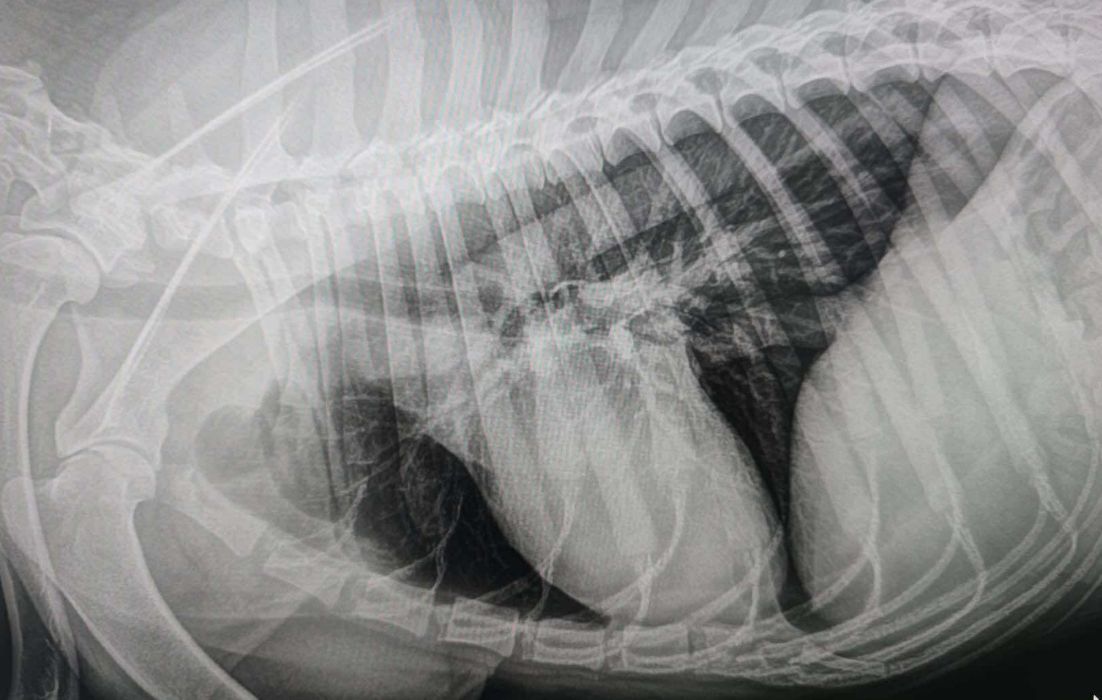

Leider gibt es traurige Nachrichten von ARON aus Rumänien. Bei dem tollen Schäfi wurde ein Tumor diagnostiziert. In der Klinik wurden Röntgenaufnahmen gemacht, die gezeigt haben, dass sich bereits Lungenmetastasen gebildet haben.